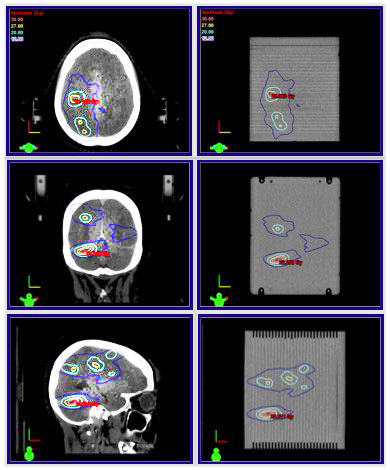

Cirs 037多病灶SRS治療計劃QA模體,Multi-Lesion Brain QA Phantom為具有多個靶標(biāo)的單個等中心計劃提供了快速、全面的薄膜劑量學(xué)質(zhì)量保證的獨特解決方案。該模型可用于徹底驗證多病變治療方法

Cirs 037多病變腦QA模型,Cirs 037多病灶SRS治療計劃QA模體型呈矩形,圓角可最大限度地減少 CT 偽影,并且尺寸足夠大以覆蓋腦解剖結(jié)構(gòu)變化。模擬腦組織的線性衰減在真實組織的 1% 以內(nèi),從 50 keV 到 15 MeV。

該模型具有兩對不對稱嵌入基準(zhǔn)標(biāo)記,并在模型等中心處將中心基準(zhǔn)分成兩半,以在照射前成像期間為您提供幫助。您還可以對齊成像基準(zhǔn)點(來自 CBCT、ExacTrac? 或 kV 圖像),并將它們與模型的參考圖像進行比較,以便更準(zhǔn)確地將模型與直線加速器沙發(fā)頂部進行位移。

該模型以 5 毫米的增量接收多達 29 個位置的放射致變色膠片。預(yù)裝聚酯薄膜片可在不影響敏感幾何形狀的情況下靈活地放置薄膜。幻影側(cè)面的外部凹槽和標(biāo)記有助于將薄膜輕松定位在所需位置,以覆蓋特定病變。膠片允許單獨審查多個計劃目標(biāo)卷 (PTV)。

使用多病變腦模型簡化SIMT計劃的膠片QA

Cirs 037多病變腦QA模型產(chǎn)品規(guī)格:

外形尺寸: 150 mm (寬) x190 mm (高) x 170 mm (長)

重量: 5公斤(11磅)

板厚:

頂板和底板: 15 mm墊片: 4.7 mm

膠片尺寸:167 毫米 x 150 毫米

材料: 腦等效環(huán)氧樹脂

聚酯片材(PET) 29 個,0.3 毫米厚